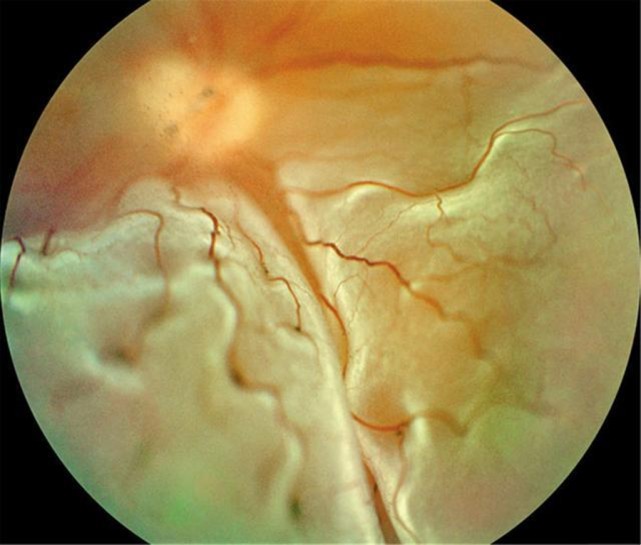

眼和面部

有一部分马凡氏综合征患者会出现眼部不适,轻者出现畏光、闪光感,重者出现晶状体脱位、异位、高度近视、甚至视网膜剥离。